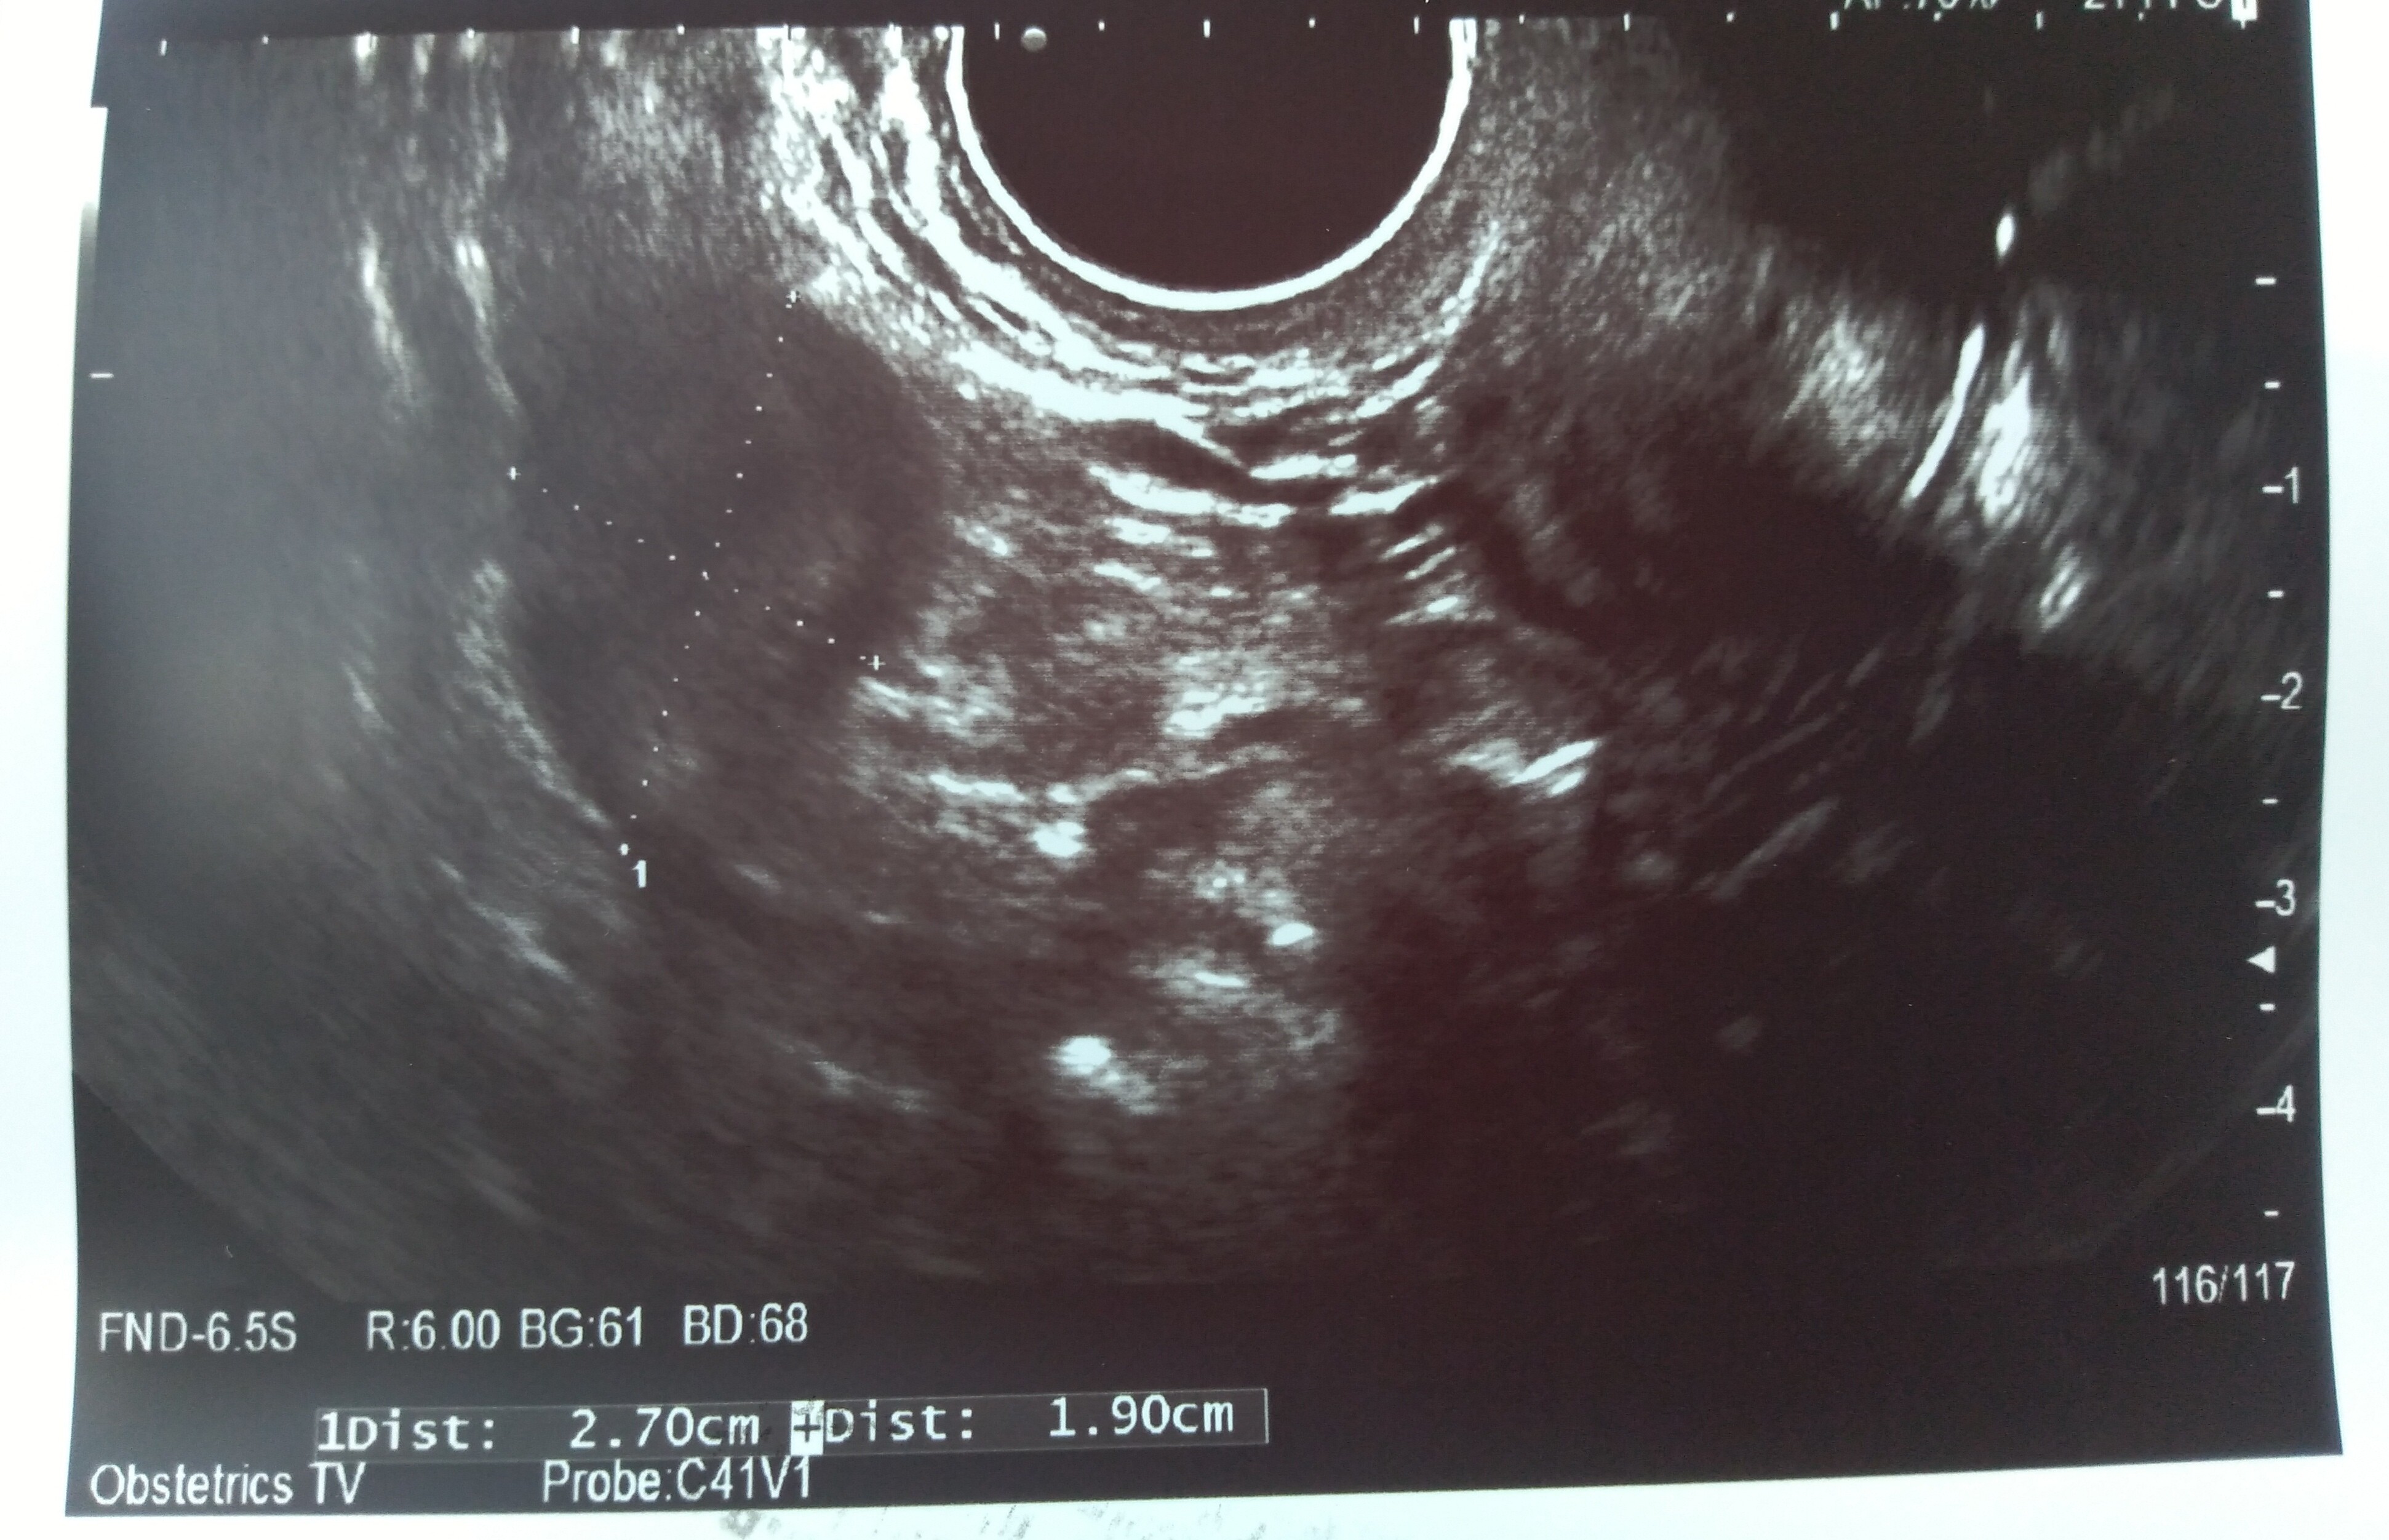

Ja w sumie sama nie wiem jaka wielkość bo lekarka mówiła 8 na 5 mm. Mówiła, że mam parę krwiaków w sumie. Ale na zdjęciu jest też coś na 2,7cm na 1,9 cm. Tylko z tego wszystkiego już sama nie wiem co. Czy to krwiak czy co. Pokaże Ci zdjęcia. Zobacz które u Ciebie podobnie wyglądało?Nie mam zdjęcia, ale z tego co widziałam na ekranie to ok 3 cm na 2,5 cm. Lekarz określił go jako nadkosmówkowego ale w internatach jest mowa tylko o podkosmówkowych. Na razie jestem w szpitalu na obserwacji, wiec zobaczymy. Ale jest też jasna strona medalu, wg OM 7 + 4 i to samo z usg. W poprzednich ciążach nie widziałam serduszka a tu było, wiec leżenie mi nie straszne nawet do końca, oby tylko z dzidzia było wszystko ok ❤